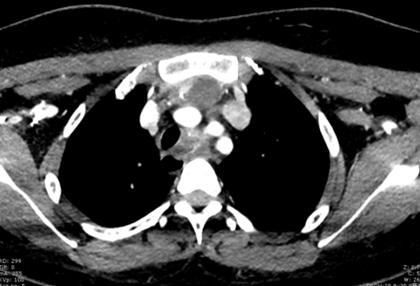

通过完善颈部增强CT、肺CT、纤维喉镜等相关检查,结果显示患者甲状腺左侧叶的巨大肿瘤已经挤压得气管严重右偏,部分腺体已经生长到了胸骨后,而且甲状腺的最下端已经深入到主动脉弓的位置。